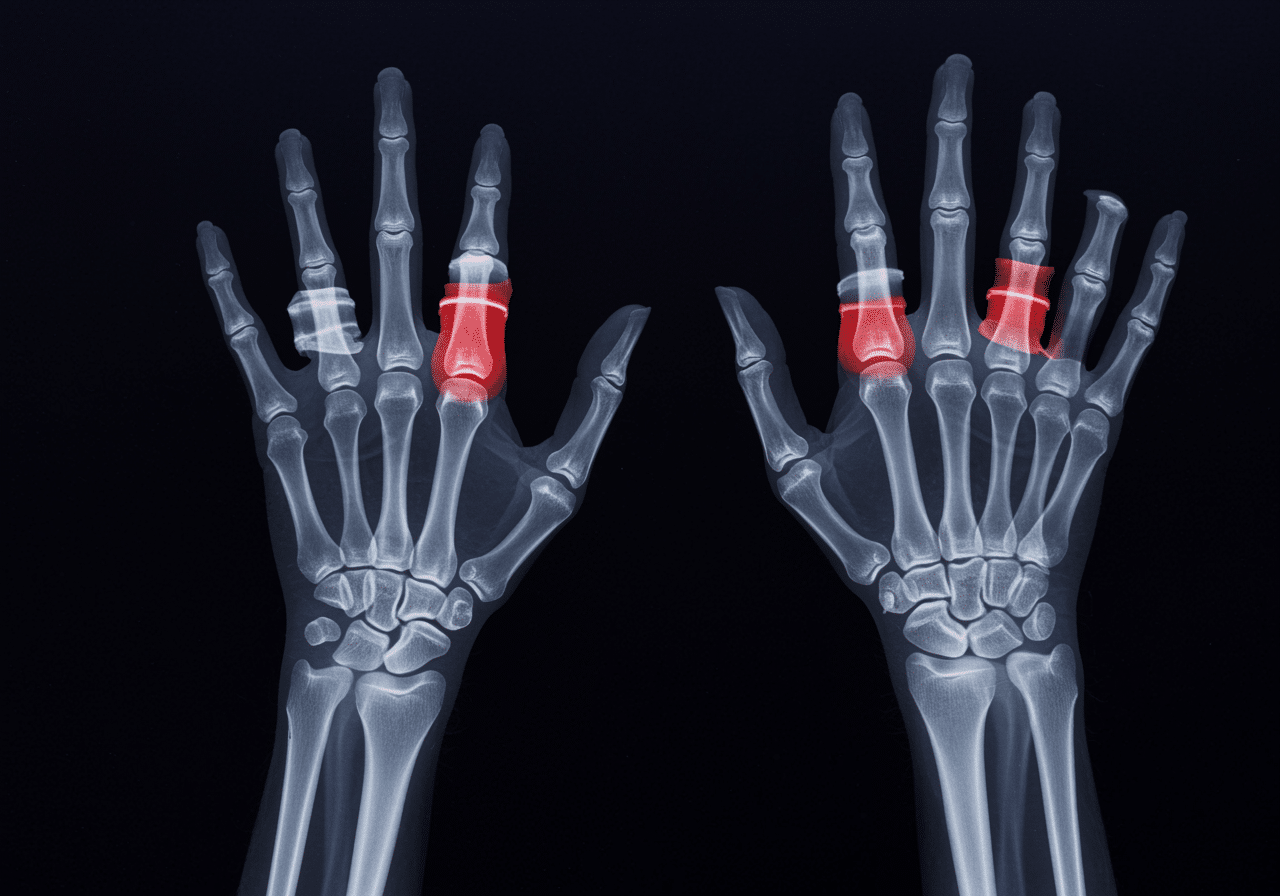

According to the American Society for Surgery of the Hand, approximately 1.5 million hand fractures occur annually in the United States, with distal radius fractures (wrist) comprising 25%, metacarpal fractures (hand) 40%, and phalangeal fractures (fingers) 35%[5]. The critical difference between optimal healing and permanent stiffness often comes down to seeking appropriate wrist, hand, and finger fractures care within the first 2-3 hours of injury. Our orthopedic emergency capabilities include immediate buddy taping, ulnar gutter splinting, thumb spica application, and sugar tong splinting techniques preventing displacement while awaiting definitive treatment.

The distinction between appropriate wrist, hand, and finger fractures treatment settings can determine whether hand function returns completely or permanent stiffness develops. Inappropriate urgent care treatment represents 35% of hand fracture complications that occur when displaced fractures require reduction or scaphoid fractures need proper immobilization[8], with true hand emergencies requiring immediate access to specialized splinting and reduction techniques unavailable in standard urgent care settings. Our emergency diagnostic imaging provides scaphoid views, oblique projections, and stress views identifying subtle fractures that standard two-view x-rays cannot detect.

Advanced imaging through our comprehensive diagnostic capabilities provides scaphoid-specific views, oblique projections identifying fifth metacarpal fractures, and true lateral wrist views assessing lunate alignment that standard PA/lateral views cannot fully visualize. For pediatric cases, our emergency physicians employ specialized growth plate assessment using Salter-Harris classification preventing physeal arrest and angular deformity that improper classification causes. This comprehensive approach explains why the American Society for Surgery of the Hand recommends emergency departments over urgent care for all displaced hand fractures, scaphoid fractures, or open wounds requiring comprehensive evaluation and specialized immobilization unavailable in limited-capability urgent care settings.